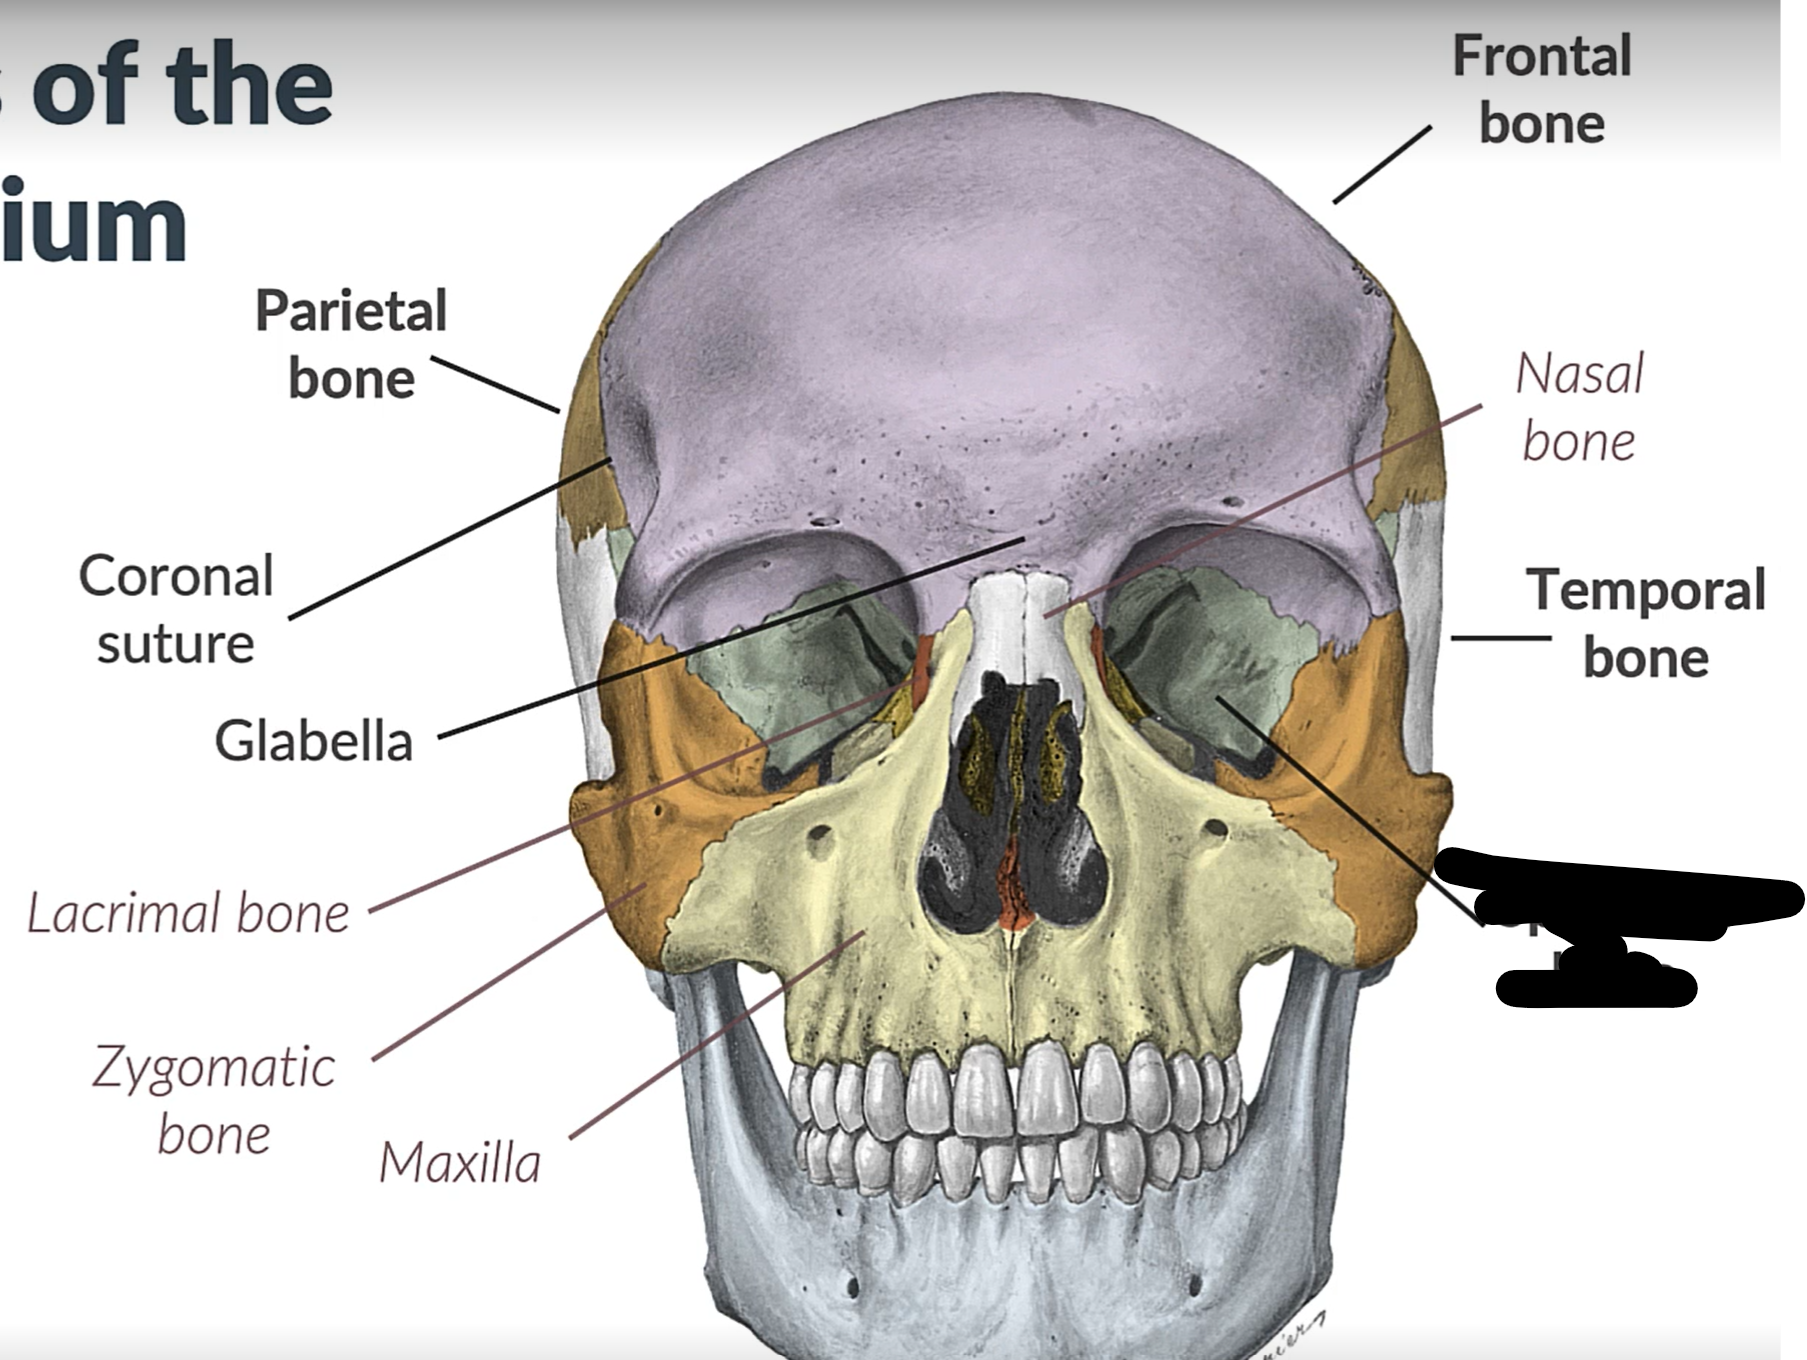

Parietal bone

Frontal bone

Temporal bone

Sphenoid bone

Zygomatic bone

Lacrimal bone

Coronal suture

Maxilla